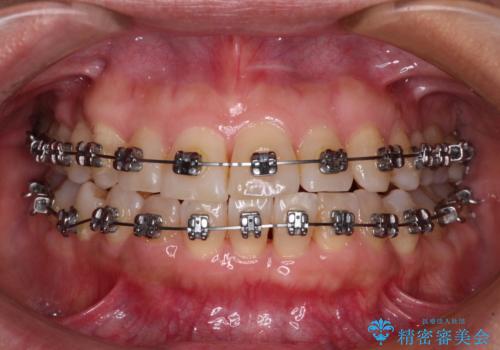

骨格のずれをカムフラージュ クロスバイトのワイヤー矯正

- メタルブラケット

- 骨格的な咬み合わせのズレ、前歯のデコボコとクロスバイトを気にして来院された患者様です。

奥歯の噛みにくさが顕著なためマウスピースではなく、ワイヤー装置による矯正治療を行うこととしました。

下顎の正中を歯1本分ずらした位置とすることで、外見上の骨格的なずれをカバーするように計画しました。

クロスバイトを改善したことで、前歯の負担が軽減し、安定して噛めるようになりました。